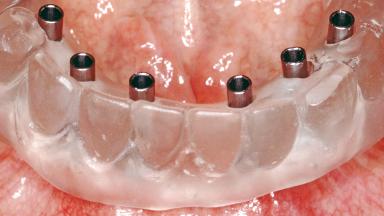

Conventional Loading of Six Implants in the Mandible and Final Restoration with a Full-Arch Metal-Ceramic FDP

A 68-year-old, completely edentulous male patient presented for evaluation and treatment options. He reported excellent general health and was taking no regular medication. He had been edentulous for approximately 12 years, having lost his teeth to periodontal disease and dental caries. The patient’s chief complaint was incompetent function. His secondary concerns included his appearance and the desire for a predictable outcome. He attributed his reduced functional capacity to his lower complete denture, which he described as poor. He was particularly concerned with the denture’s instability and poor fit. In general terms, he was satisfied with the maxillary complete prosthesis. The maxillary prosthesis was characterized by adequate retention, stability, and support, although the fit was considered less than ideal.

# of Implants 6

Type of Implants One-Piece

Defining Characteristics Fully edentulous lower jaw to be rehabilitated with two or more implants

Modality > 4 implants, extending to mental nerve region